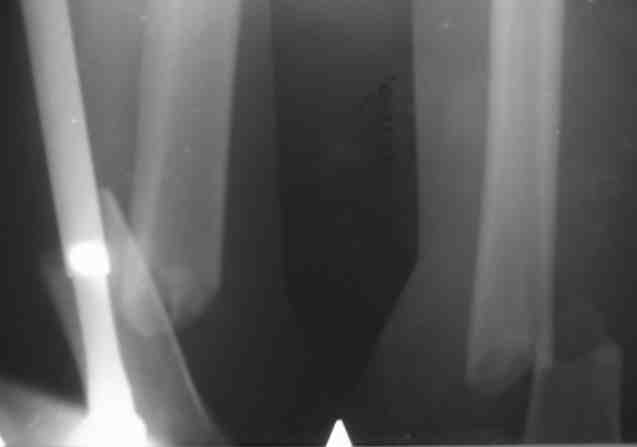

Рг в приложении.

КАН> допущенные ошибки. Спасибо. Рг в приложении.

Снимки вполне симпатичные. Единственное, по ротации не понял, уж больно неразборчивый тот, который без гвоздя.